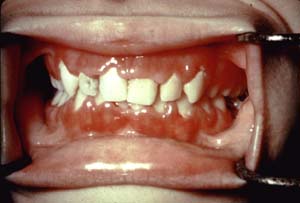

Leukemia (Blood Forming Cell Tumors)

Photo 3